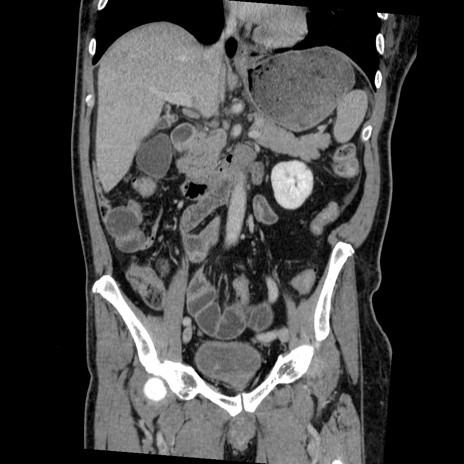

横断像

【症例】50歳代男性

【主訴】腹痛

【現病歴】AVMからの被殻出血のため回復期リハ病棟入院中。 本日午後3時頃急に下腹部痛が出現した。

【既往歴】AVM、被殻出血、虫垂炎、高血圧

【身体所見】意識晴明、左半身不全麻痺、会話の理解は良好、36.5°C、腹部:膨隆、全体に板状硬、下腹部正中に圧痛点あり、反跳痛-、筋性防御不明、右下腹部にope scar

【データ】WBC 9400、CRP 0.06